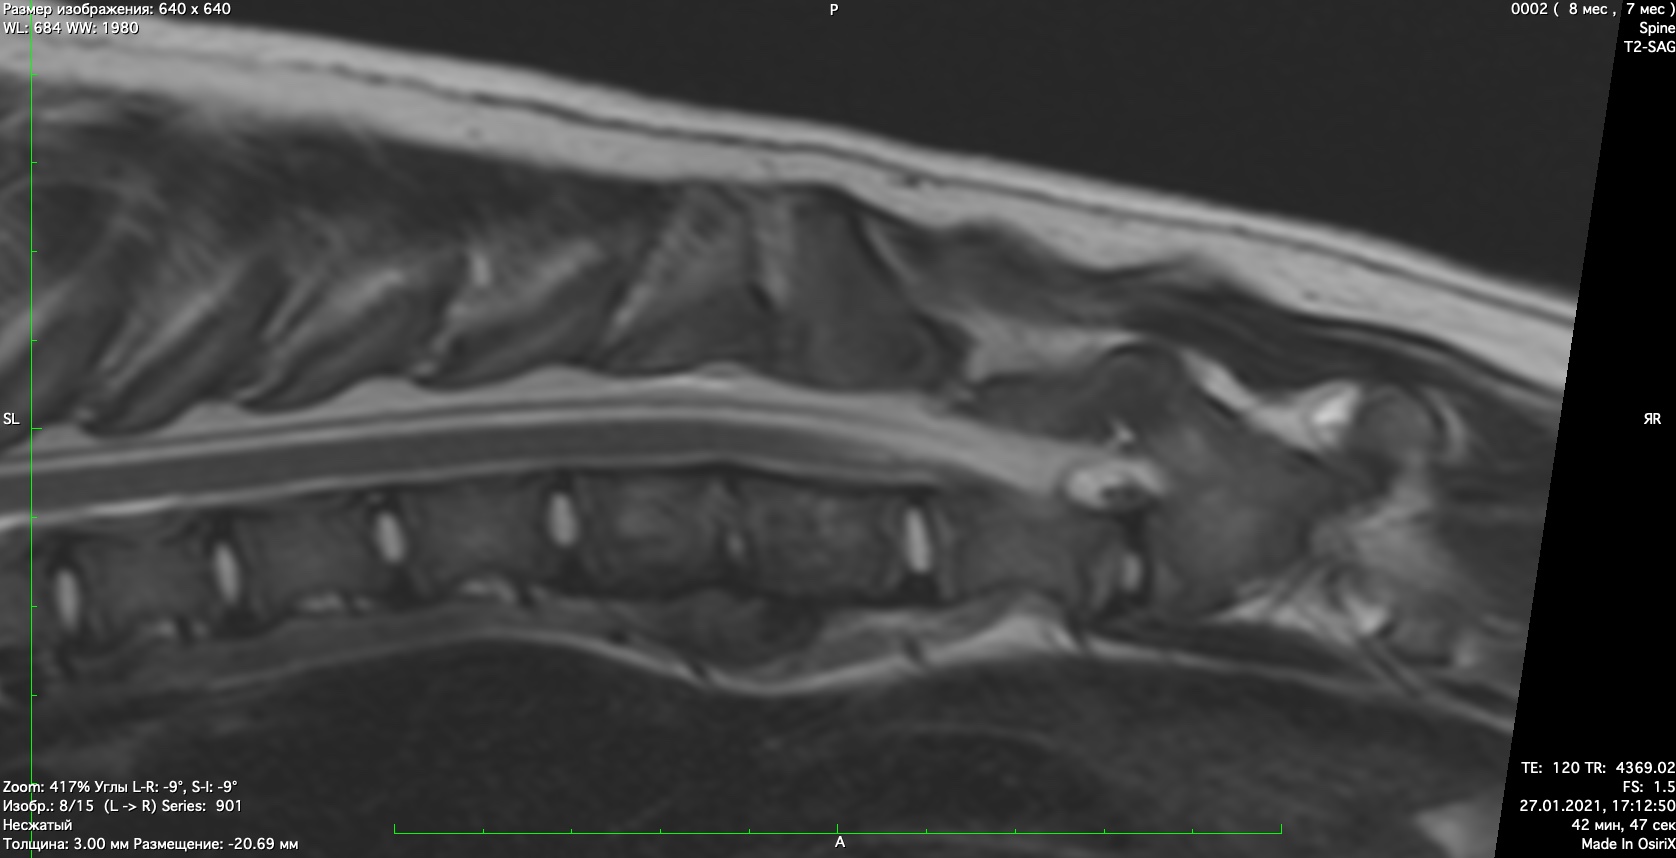

При проведении неврологического осмотра установлено- неврологический дефицит отсутствует, сильная болезненность при пальпации поясничного отдела позвоночника При проведении мрт диагностики установлено признаки воспаления позвонков поставлен диагноз-дискоспондиллит. начато лечение дискоспондиллита -антибиотиками